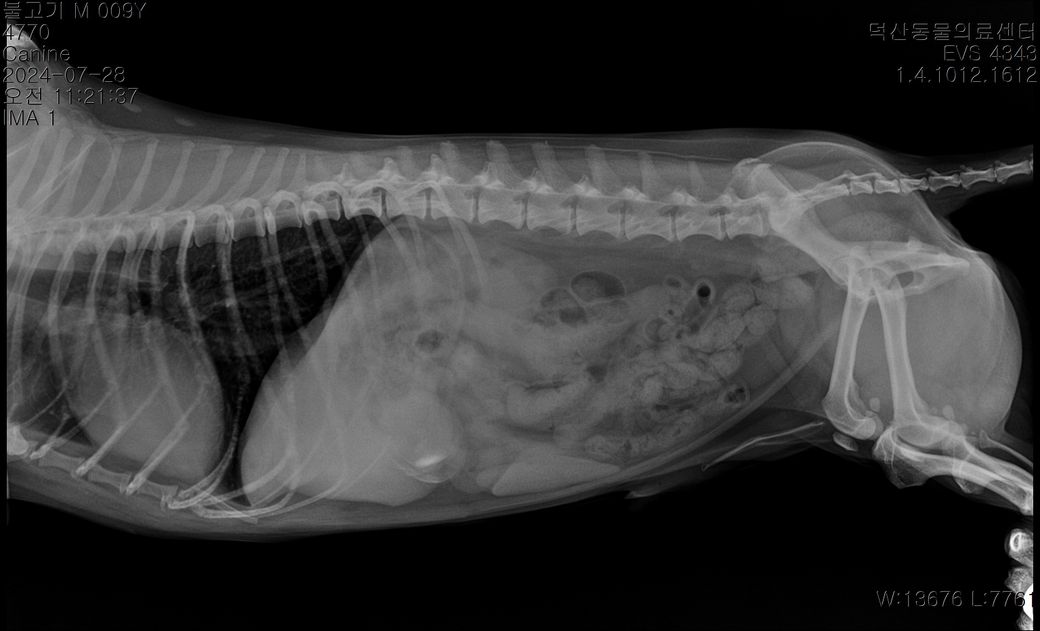

강아지 담낭 찌꺼기가 차있다고 하는데 수술해야 하는 정도일까요? 초음파로도 보인다고 합니다

엑스레이 사진에서 저정도 보이면 바로 수술해야한다고 하는데 걱정입니다

X-ray만으로는 담낭 점액종이나 종양 여부를 확인할 수 없습니다.

복부초음파로 보면 그래도 담낭의 상태를 확인 할 수 있으니 일차적으로 복부초음파 검사와 담낭과 관련된 수치 검사 하시는 것을 권유드립니다.

엑스레이 검사 결과는 담낭 제거 수술의 기준이 되지 못합니다. 초음파 검사와 다른 검사의 결과를 모두 확인한 주치의가 필요하다고 판단했다면 그 검사들에서 수술의 합당한 근거가 있었을 것으로 추정되니 주치의와 심도 깊은 상담 받으시기 바랍니다. 술 후 입원 기간은 환자의 술후 반응에 따라 다르나 통상 1~2주 정도 소요되는게 일반적입니다.